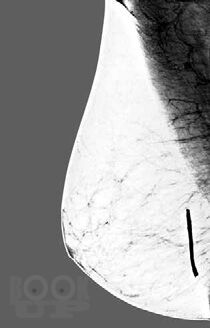

Лучевая диагностика заболеваний молочной железы

В одной книге представлен обзор случаев типичных проявлений заболеваний молочной железы, выявляемых при маммографии, ультразвуковом исследовании и магнитно-

резонансной томографии. Дано краткое описание того, как выполнить биопсию и другие процедуры на молочной железе с использованием каждой из трех методик. Простой формат,

четкая структура материала и ссылки на источник в конце описания каждого случая помогут начинающему врачу принимать правильные решения.